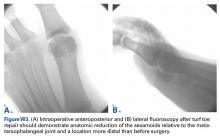

The collateral ligaments are often torn away from the metatarsal head during the initial dissection and the plantar plate tear is distal to the sesamoid complex. The soft tissue defect in the plantar complex must be closed distal to the sesamoids followed by advancement of the plantar plate to the proximal phalanx in a distal to proximal fashion and advancement of the medial capsule. The plantar incision is made along the lateral border of hallux MTP-sesamoid complex just lateral to the weight-bearing surface of the hallux and the plantar lateral cutaneous nerve is carefully dissected and retracted out of the way. Sutures are placed in a figure-of-eight fashion through the plantar capsule and plantar plate starting lateral to medial to reduce injury to the nerve. If the tear cannot be primarily repaired due to inadequate healthy tissue, a plantar plate advancement can be performed directly onto the base of the proximal phalanx using drill holes or suture anchors. Proper alignment and motion of the sesamoids should be verified with fluoroscopy and compared to the contralateral hallux (Figures W3A, W3B).It is important to recognize that not all turf toe injuries involve pure hyperextension on artificial playing surfaces. In recent years, we have found an increasing rate of medial variant turf toe injuries in which a forceful valgus stress on the hallux leads to rupture of the medial collateral ligament, medial or plantar-medial capsule, and/or abductor halluces. Medial variant turf toe can lead to progressive hallux valgus and a traumatic bunion with a significant loss of push-off strength and difficulty with cutting maneuvers. Surgical treatment requires a modified McBride bunionectomy with adductor tenotomy and direct repair of the medial soft tissue defect.